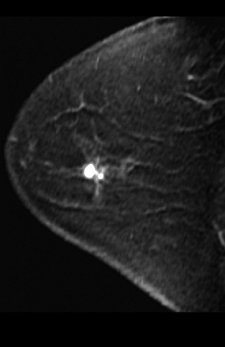

| A 49-year-old woman with mammographically occult contralateral breast cancer detected on MRI. Above, initial contrast-enhanced sagittal MR image. Below, CAD overlay shows lesion as having significant enhancement and mixed pattern of washout, plateau, and persistent delayed enhancement. If pixel value on delayed series decreases by more than 10% of its immediate contrast-enhanced value, that pixel is color-coded red on monitor, indicating washout of contrast material. If pixel value increases by more than 10%, it is color-coded blue on monitor, indicating persistent enhancement. If pixel value does not change in either direction by more than 10%, it is color-coded green for plateau enhancement. |

According to the results, 24 lesions were identified by pathology as benign and nine were malignant. "All malignant lesions showed significant enhancement using the program at all thresholds, producing a sensitivity of 100%," the authors wrote.

"False-positive rates for the computer-aided assessment compared with the original radiologist assessment were reduced by 25% at a 50% threshold, 33% at an 80% threshold, and 50% at a 100% threshold for enhancement," they added.